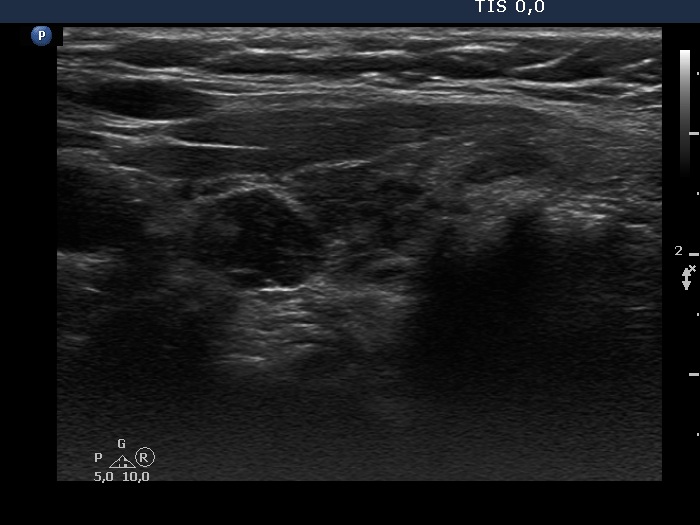

Discrete lesion or nodule in Hashimoto's thyroiditis - case 31 (1210) (ultrasonographic picture 6)

Left lobe, another longitudinal view.